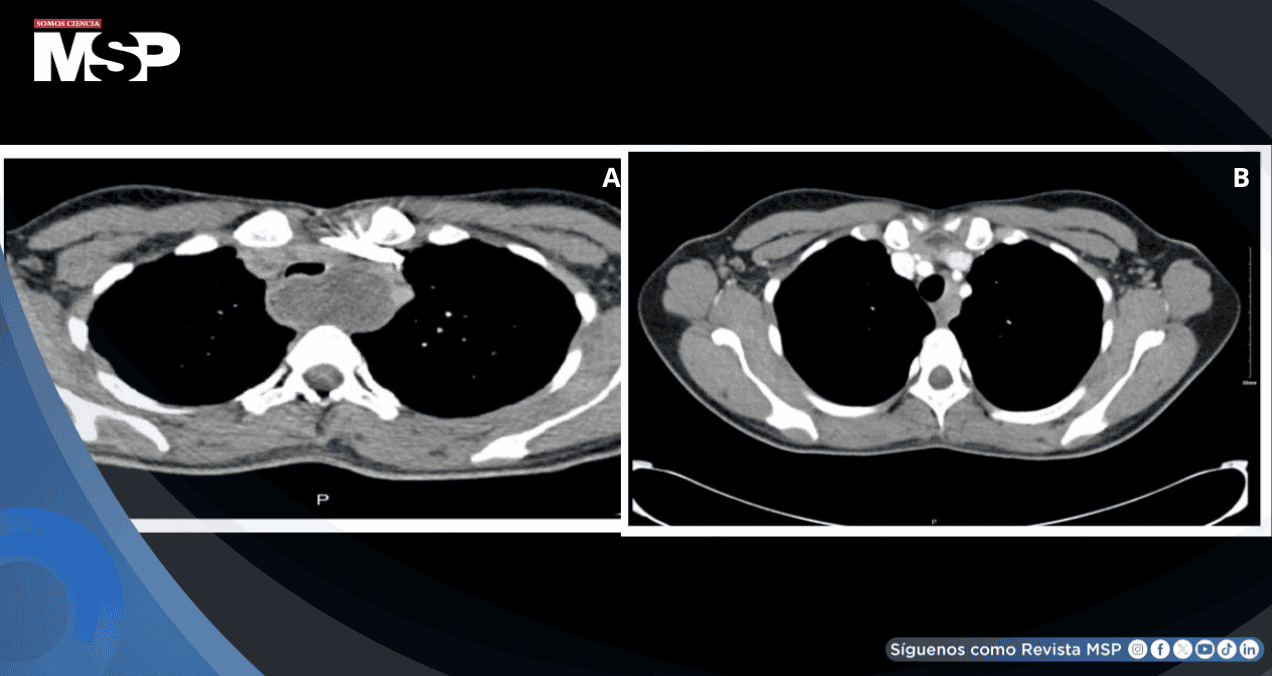

El seguimiento imagenológico programado se realizó seis semanas después del parto mediante tomografía computarizada de tórax.

Los resultados fueron notables y sorprendentes: la lesión quística había experimentado una reducción significativa en su tamaño, midiendo ahora apenas 1 centímetro, lo que representaba una disminución del 80% respecto a su tamaño inicial.

Durante todo el período de observación, la paciente permaneció completamente asintomática, sin reportar síntomas respiratorios, dolor torácico o cualquier otra manifestación clínica relacionada.